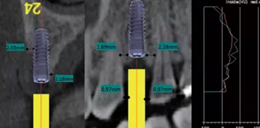

術(shù)前拍攝錐形束CT并做種植方案規(guī)劃。從圈紅處可以看出頰側(cè)骨組織不夠致密,建議備完孔后再做小翻瓣以觀察窩洞頸部的情況,圖2中的粉紅色及藍色HU值曲線顯示種植體內(nèi)部及其周圍的骨密度不高,為四類骨質(zhì),因此術(shù)中應(yīng)通過控制備孔的直徑或深度,以使種植體獲得較佳的初期穩(wěn)定性。

圖2 種植方案的規(guī)劃:a.頰舌側(cè)方向的截面圖,頰側(cè)圈紅處骨質(zhì)較疏松;b.近遠中方向截面圖;c.種植體周圍的骨密度